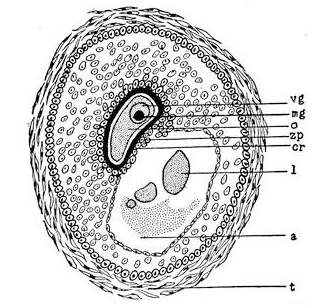

Mons of Venus, labia majora, minora, vestibule, bulbs, clitoris, Bartholinian glands, hymen, vagina, uterus, broad and round ligaments, viiitubes, ovaries, Graafian follicle, ovum.

Function of ovaries, ovum, Graafian follicle, tubes, menstruation, function of uterus, female ejaculation, function of vagina, Bartholinian glands, of clitoris, course of the sexual act.

Before the Wolffian body has yet degenerated the mesothelial cells overlying the free surface of that body, at its upper part, and at the ventro-mesial side, assume a high columnar form and form an elongated swelling, known as the internal genital ridge. As the degeneration of the Wolffian body proceeds the genital ridge is differentiated into the indifferent sexual gland, by producing a projection upon the wall of the coelom or body cavity. This prominence is attached to the surface of the Wolffian body by a fold of the peritoneum. At this stage there is no distinction of sex. The sexual gland represents the indifferent type of the sexual apparatus.

The ovary is produced from the asexual stage by the following metamorphosis. The mesothelial cells on the peritoneal surface of the sexual gland change into the germinal epithelium and form the so-called egg-columns or sexual cord which represent the primitive ova.